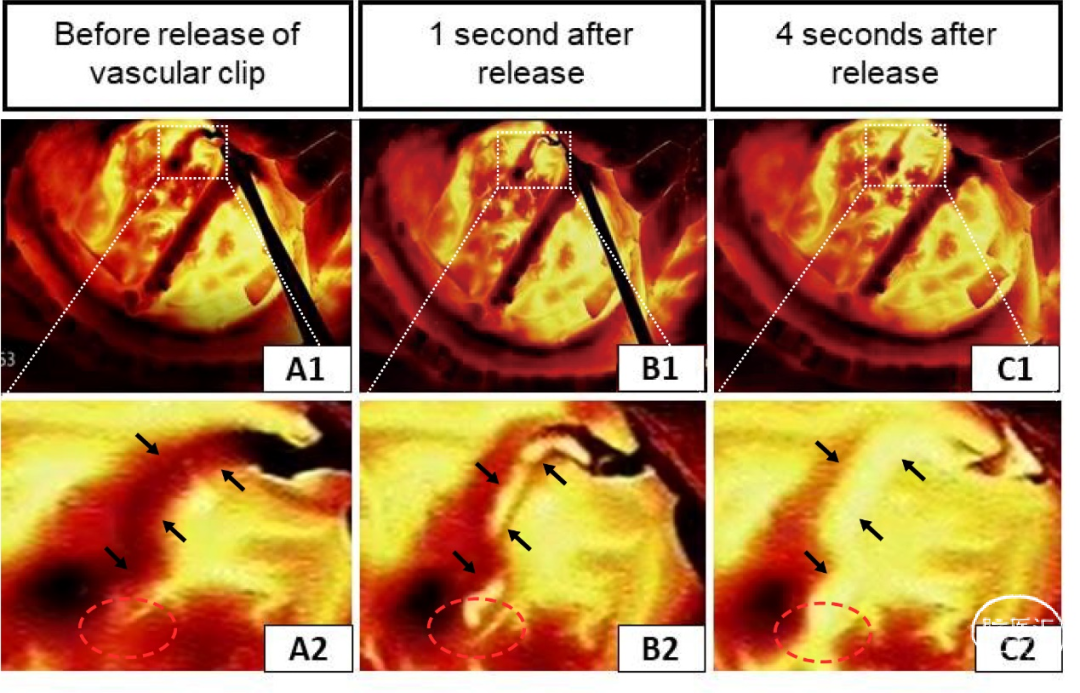

图2展示了一例右侧STA-MCA(M4)旁路手术期间获得的红外热成像图像。在释放血管阻塞夹之前,吻合口和供体血管(STA)的温度较低,几乎没有血液流经吻合口,对应于图2A1、2中的黑暗区域。在释放血管夹后,从供体血管流入吻合口的血液温度相对于大脑皮层较低,在图2B1、2中清晰可见,表明吻合口通畅良好。此外,远端分支血管在热成像中出现了一瞬间的黑暗影像,表明从供体血管向大脑皮层有正向的血流。图2C1、2显示了释放血管阻塞夹后4秒的情况。所有血管都变成了彩色。证明了再灌注的成功,并表明红外热成像可以正确评估吻合口通畅性。

图2. 右侧STA-大脑中动脉(M4)分流手术期间的红外热成像。(A1-C1)血管夹释放前和释放后不久的红外热成像图像。(A2-C2)放大的视图与上图相对应(黑色箭头表示STA,红色圆圈表示供体和受体血管的吻合处)。